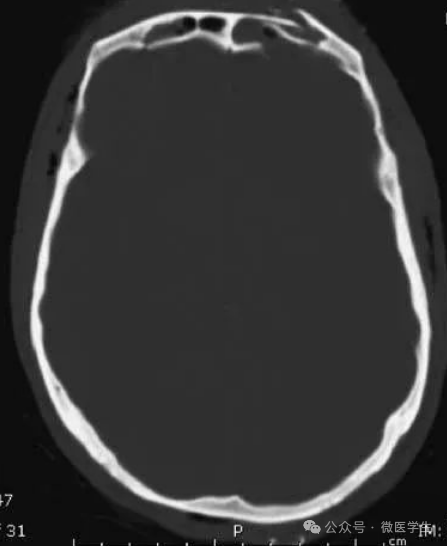

颅脑CT常用的三个窗(图A-C):

- 图A:骨窗(the bone window)

- 图B:脑窗(the brain window)

- 图C:血窗(the blood window)

图A:骨窗;主要用于明确骨折、窦腔病变、颅内积气。

图B:脑窗;可清晰显示灰白质,可发现中风的早期征象或其他导致脑水肿等表现的病变。

图C:血窗;更利于显示硬膜下或颅内出血。

本例表现:骨窗示:右顶骨骨折;三个窗均示:软组织水肿并皮下积气;血窗:少量硬膜下血肿。